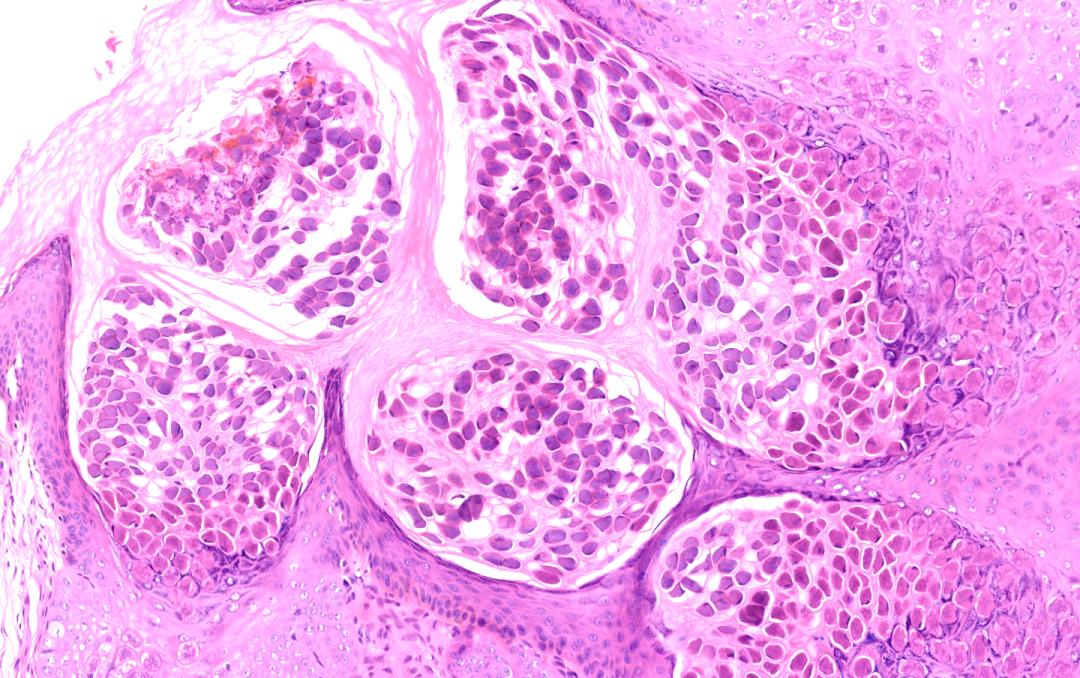

石榴派对

一位病毒性皮肤病(传染性软疣)的皮肤组织病理照,多发的软疣小体像石榴籽一样紧紧抱在一起。我们的身体是团结的,只有“不讲武德”的病毒,通过抱团来入侵与散播。